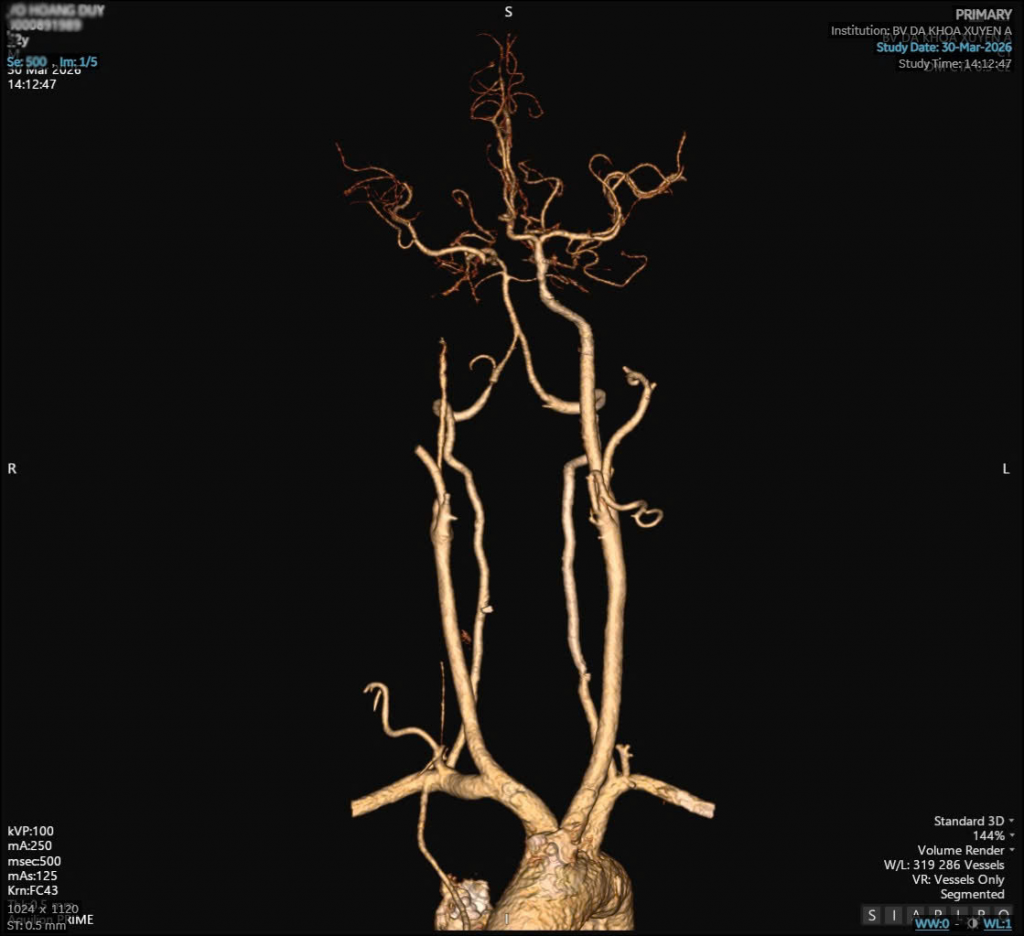

Hình ảnh phim CT bệnh nhân D

Kết quả chụp MRI não chẩn đoán anh bị nhồi máu não vùng cầu não, hẹp động mạch cảnh và có túi phình nhỏ. Sau khi được dùng thuốc tiêu sợi huyết, tình trạng của bệnh nhân cải thiện rõ rệt. Sau 5 ngày điều trị, anh đã hồi phục tốt, không còn chóng mặt, sức cơ trở lại bình thường. Tuy nhiên, bác sĩ khuyến cáo anh cần kiểm soát huyết áp chặt chẽ và tránh gắng sức để phòng nguy cơ vỡ túi phình.